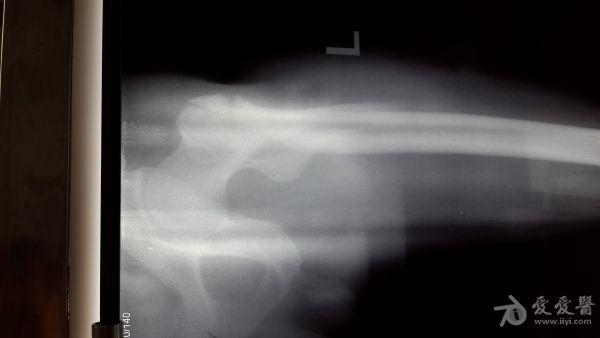

股骨粗隆间粉碎特性骨折的手术方案

男性,65岁